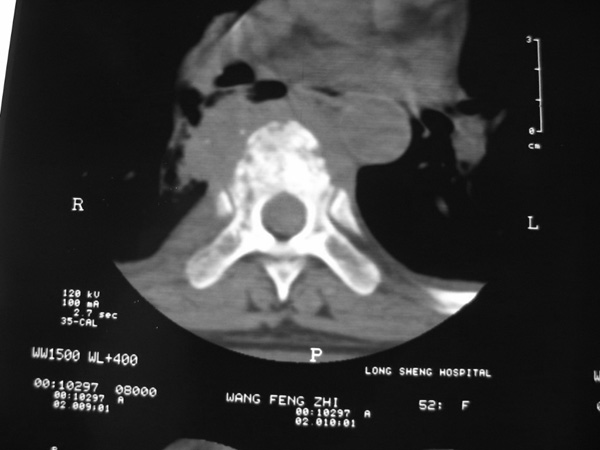

女,45岁,胸背部疼痛2个月。t6、7胸椎病变。

椎旁肿胀的软组织内可见气泡影,对脊柱的化脓性和结核性的鉴别有帮助吗?

支持胸椎结核伴冷脓肿伴双侧胸腔积液.为何无肺窗.

支持胸椎结核伴冷脓肿伴双侧胸腔积液

胸椎结核伴冷脓肿伴双侧胸腔积液

胸椎体骨质破坏伴死骨形成,椎周环状软组织肿胀,范围较长,考虑胸椎结核伴冷脓肿形成。鉴别;1转移性肿瘤;椎弓根骨质破坏多见,软组织肿块局限。椎间隙尚存。有原发肿瘤病史。2,淋巴瘤;骨质破坏 然骨皮质轮廓线尚存,当椎管骨示环状软组织影时有一定特异性。病变较局限。建议mri增强,观察冷脓肿与软组织肿块很有帮助。